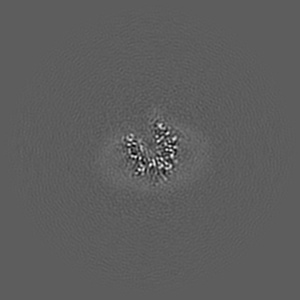

Cryo-EM structure of the mammalian peptide transporter PepT2 bound to cefadroxil

Sample: Complex of the mammalian peptide transporter PepT2 with nanobody and bound cefadroxil

Structural basis for antibiotic transport and inhibition in PepT2.

Parker JL , Deme JC , Lichtinger SM , Kuteyi G, Biggin PC , Lea SM , Newstead S

(2024) Nat Commun , 15 , 8755 - 8755